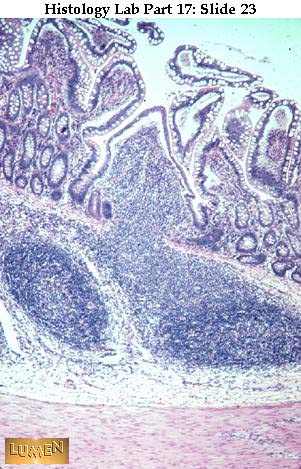

Slide 23

Wall of ileum, with villi and short crypts in the mucosa. There are now also Peyer's patches (dense lymphatic tissue which extends from the submucosa up into the mucosa, thus interrupting the thin, pink muscularis mucosae).